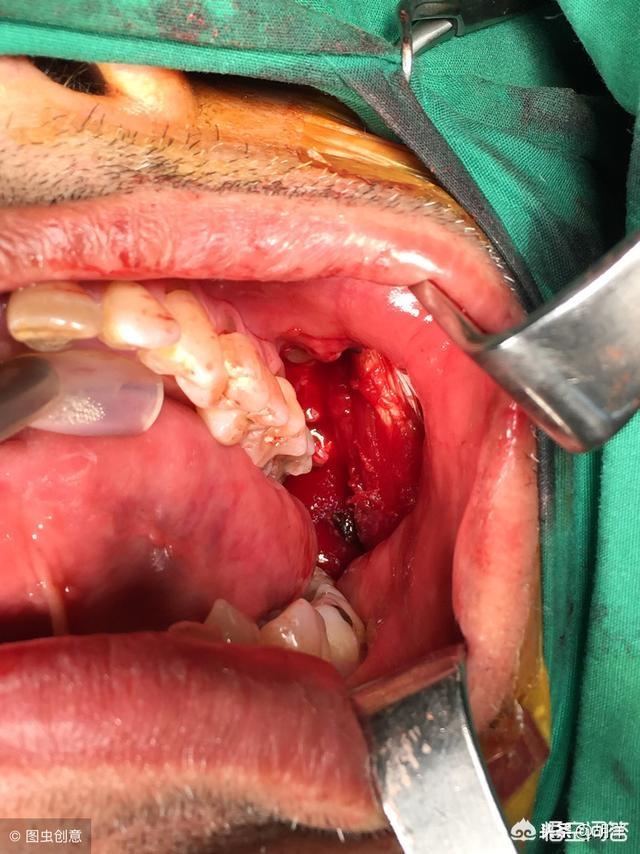

最近有文章称,年千亿收入规模的软性毒品槟榔,正危害食用者生命健康。确实有大量的研究表明,经常咀嚼槟榔会提高口腔癌的发病率,使患口腔癌的风险上升8.4-9.9倍。印度是槟榔的消耗大国,同时也是口腔癌发病率最高的国家。很多人说:“十个口腔癌,九个嚼槟榔”,事实上早在2003年世界卫生组织下属的国际癌症研究中心就已经将槟榔认定为一级致癌物。所谓一级致癌物指的是对人体有明确的致癌性的物质或者混合物,比如甲醛、石棉、二恶英、酒精、烟草等都是一级致癌物。槟榔当中含有的一些生物碱具有细胞毒性,槟榔碱还能在咀嚼的过程中产生亚硝胺类化合物(致癌物),加快上皮细胞的凋亡,长此以往就会导致癌症的发生。而且,咀嚼槟榔的动作也会导致口腔黏膜的一些机械性损伤,长期可导致口腔黏膜下的纤维性变,有可能引发癌变。此外许多槟榔在加工过程中会加入各种添加剂,口腔直接接触,增加患癌风险。如果抽烟加嚼槟榔两者合并,更容易引起口腔癌、喉癌、咽癌和食道癌。